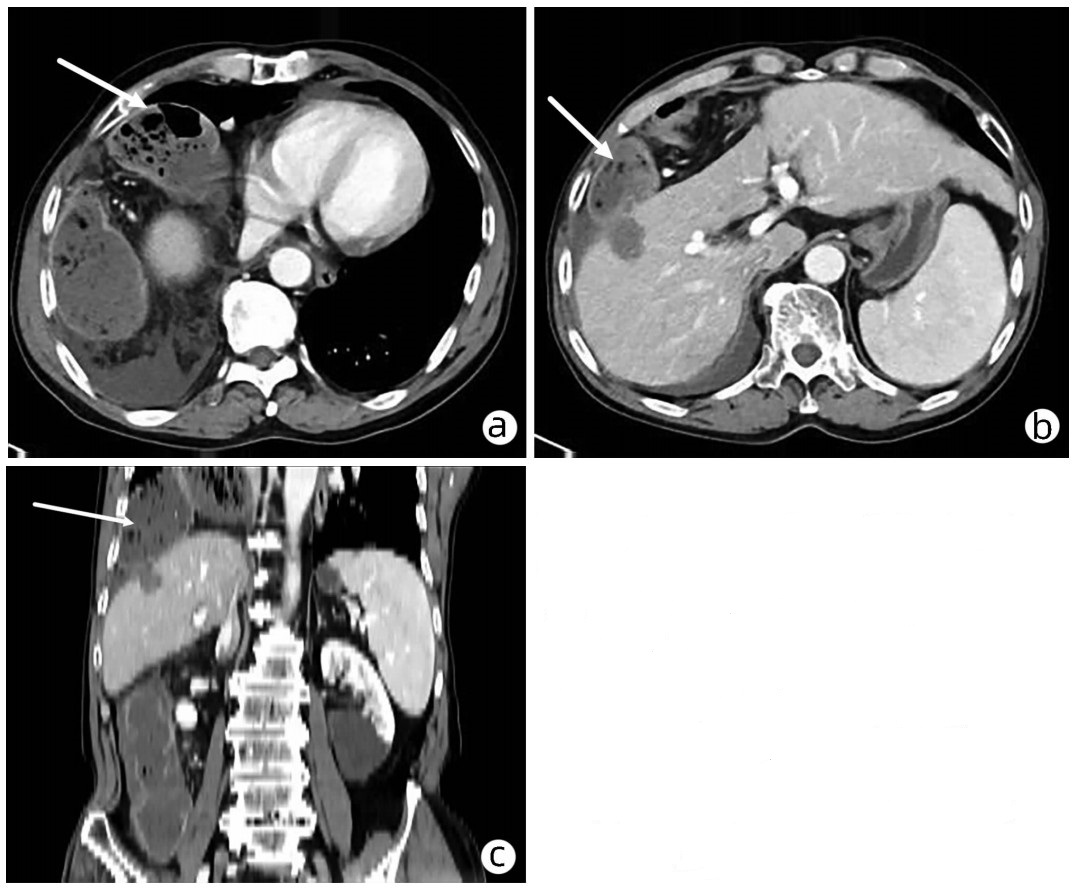

肝细胞癌合并胆管癌栓1例报告

摘要(803) HTML (455) PDF (3665KB)(82)